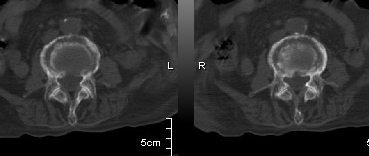

男:89岁因外伤后2天行ct检查。请各位战友讨论图中所指是否是骨折和形成该影像的原因(扫描层面位于椎体中份)。

椎体压缩性骨折,结肠淤张,胀气说明肯定骨折.

椎体压缩骨折,结肠淤张,应该肯定,交感神经有损伤.

老年性骨质疏松,椎体前缘出现双边征支持压缩骨折。椎体骨质稀疏,似有破坏,警惕溶骨性骨转移。

我的报告1:腰椎骨质退行性改变。

2:t12改变考虑压缩骨折?请结合临床。